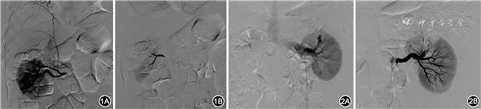

15次造影中仅1例次可见明确造影剂外溢,表现为造影剂溢出血管外,进入术区残腔或肾周间隙;3例次可见肾动静脉瘘形成,表现为肾动脉分支与邻近静脉直接相通,动脉期肾静脉分支早显,肾动脉分支增粗,肾动脉分支与静脉分支并行出现,即呈“双轨征”表现;12例次可见局部动脉管壁不光整、远端动脉扩张(图1);11例患者伴假性动脉瘤形成,表现为与出血动脉分支相连的囊状或柱状瘤样影,突出于载瘤动脉一侧,相关动脉分支增粗,栓塞后责任动脉均完全闭塞(图2)。上述DSA表现,或单独出现,或多种表现共存。出血动脉与手术部位相关,为左肾动脉上段动脉9例次,右肾动脉上段动脉6例次。

1973年,Bookstein和Ernst[9]首次采用肾动脉栓塞术治疗肾出血,取得良好的疗效,因其创伤小且能最大程度地保留正常肾单位等优点,逐渐被医生及患者认可并推广。进行栓塞止血前,首先行DSA,根据DSA表现决定是否行血管内栓塞。因此,准确认识并掌握DSA表现至关重要,文献报道[10]的医源性肾动脉出血的DSA表现主要包括:造影剂外溢、假性动脉瘤形成、动静脉瘘、局部动脉不规则扩张等。本组病例DSA表现为造影剂外溢、大小不等的假性动脉瘤形成、动静脉瘘及局部动脉不规则扩张,与文献报道的相同。但出现直接征象造影剂外溢的的患者较少,对于没有明显造影剂外渗的病例,笔者的经验是,局部扩张的动脉分支及载假性动脉瘤的分支即是栓塞的靶动脉,对上述动脉进行栓塞后,患者出血均停止。因此,对于有明确活动性出血的患者,造影发现术区血管异常,考虑为出血责任血管,应超选后进行栓塞。动脉栓塞止血所用的血管内栓塞的材料主要有微弹簧圈、明胶海绵颗粒、PVA颗粒等[10, 11]。本组患者使用2 mm×3 mm及2 mm×4 mm塔形微弹簧圈栓塞,必要时补充明胶海绵颗粒,均达到良好的栓塞效果,不建议使用颗粒型栓塞剂单独栓塞,以防出现异位栓塞。